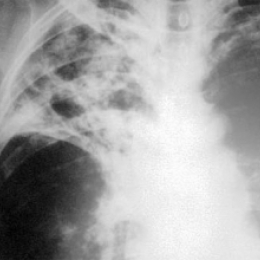

Заболевание лёгких у людей, живущих в неблагоприятных условиях

В настоящее время туберкулез, как правило, встречается только у определенных групп людей: алкоголики, наркоманы, ВИЧ-инфицированные, люди с низким уровнем жизни. Дело в том, что туберкулез передается не только контактным, но и воздушно-капельным путем. Т.е., при разговоре с человеком, болеющим туберкулезом, существует определенный риск заражения собеседника. Таким образом, если туберкулезом заболевает один из членов семьи, все остальные члены находятся в зоне риска. Поэтому, чтобы снизить риск заражения окружающих, больному необходимо использовать индивидуальные средства, препятствующие распространению бактерий туберкулеза: защитные маски, стараться прикрываться при кашле, чихании, мыть руки.

Причина заболевания людей с низким уровнем заключается в резком иммунодефиците, которым они страдают. Дело в том, что носителями туберкулезной бактерии является подавляющая часть населения, но не каждый болеет туберкулезом, так как иммунитет человека способен бороться с этим заболеванием. Если у человека иммунитет снижен, то бактерии начинают интенсивно размножаться, что, в конечном итоге, приводит к возникновению болезни.

В дальнейшем, если туберкулез продолжает прогрессировать, возможно развитие осложнений. В первую очередь, поражается легочная ткань и плевра, что приводит к появлению кровохарканья и возникновению сильных болей в области груди при дыхании.